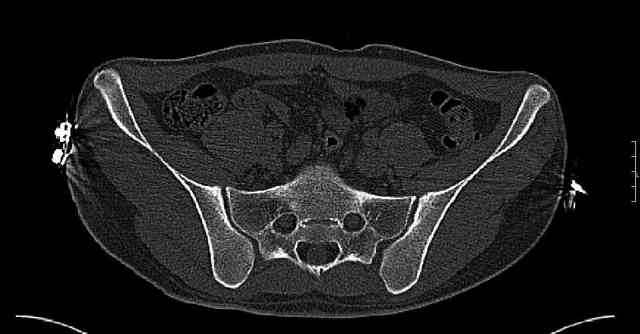

Some more images. Does it help to guess which part of the acetabulum is displaced?

Normal appearing SI joints and a healed posterior column limb... my bet's on caudal segment displacement.

The anterior element of the fracture is so low and the anterior roof arc angle must be at least 60 deg.

The posterior element is so minmally undisplaced. There is good congruence of the joint, and to top it all, 6 weeks have passed. If you consider ORIF now, I don't expect that much improvement could be accomplished. Not to mention the need for extensive approaches with their morbidity.

While not claiming to have the best 3D brain around, it appears to me from the limited images available, that the caudal segment is stable from the symphysis to the SI joint on the fracture side. I would love to see the rest of the transverse CT images to see where the fracture line actually exits posteriorly on both the inner and outer tables of the ilium. In my hands,